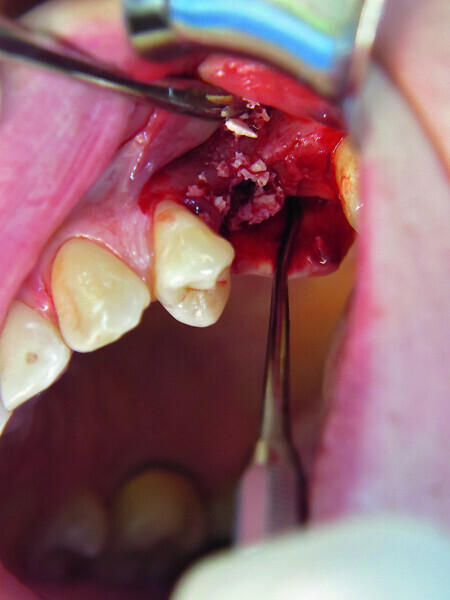

Fig. 10: 3-D augmentation using NanoBone.